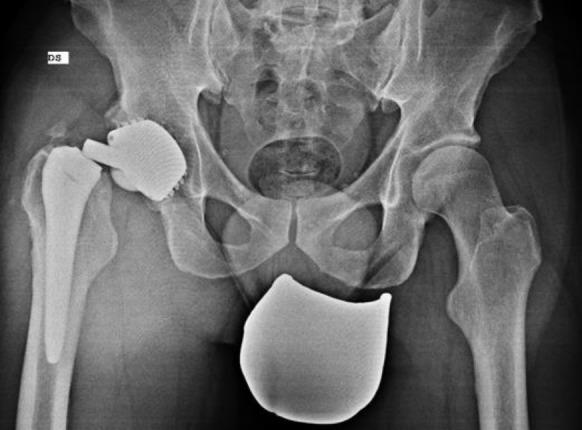

模块化牢固固定型髋关节翻修柄骨折:一例报告及文献综述

Modular Well-Fixed Hip Revision Stem Fracture: A Case Report and Literature Review.

This study presents a case of repeated prosthetic fractures in a modular hip prosthesis in a 56-year-old male patient. After the initial implantation of a modular total hip prosthesis in 2006, the patient experienced two instances of prosthetic implant fractures over seventeen years. In this study, we analyze the clinical case, explore potential underlying causes of this complication, and delve into current indications and strategies for the revision of fractured prosthesis stems. The discussion is informed by a literature review and underscores the significance of selecting appropriate revision techniques to address this challenge.

摘要

本研究报告了一例56岁男性患者模块化髋关节假体反复发生假体骨折的病例。2006年首次植入模块化全髋关节假体后,该患者在十七年中经历了两次假体植入物骨折。在本研究中,我们分析了该临床病例,探讨了这种并发症的潜在根本原因,并深入研究了目前骨折假体柄翻修的适应症和策略。讨论以文献综述为依据,并强调选择合适的翻修技术来应对这一挑战的重要性。